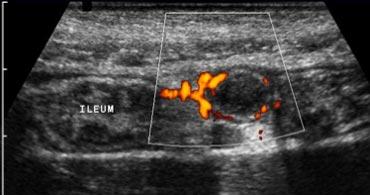

Viêm ruột thừa

Một dấu hiệu hỗ trợ khác cho viêm ruột thừa là tăng sinh mạch máu của thành ruột thừa trên siêu âm Doppler màu [1] (Hình 3b).